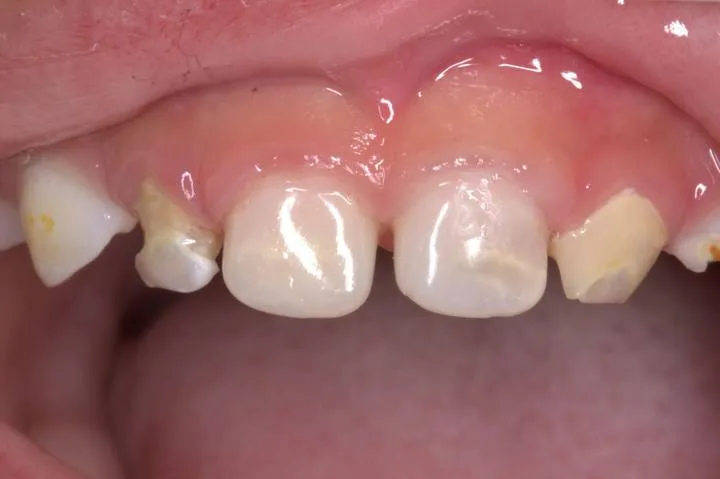

乳牙預成冠是一種(zhǒng)預先製作成型的牙(yá)冠修複(fù)體(tǐ),采用生物相(xiàng)容性材料(如醫用不鏽鋼、複(fù)合樹脂或透明氧化鋯陶瓷)製成,通過標準化尺(chǐ)寸與形態設(shè)計,貼合兒童乳牙解剖結構。這一(yī)技術(shù)以“精準修複、快速安裝、長期保護”為核心(xīn),成為乳牙大麵積缺(quē)損修複的黃金標準。

1.大麵積齲壞:齲損涉(shè)及兩個及以上牙麵,剩餘牙體不足50%。

3.發育缺陷修複:如釉(yòu)質發育不全、遺傳性牙本質疾病導致(zhì)的牙體缺損。